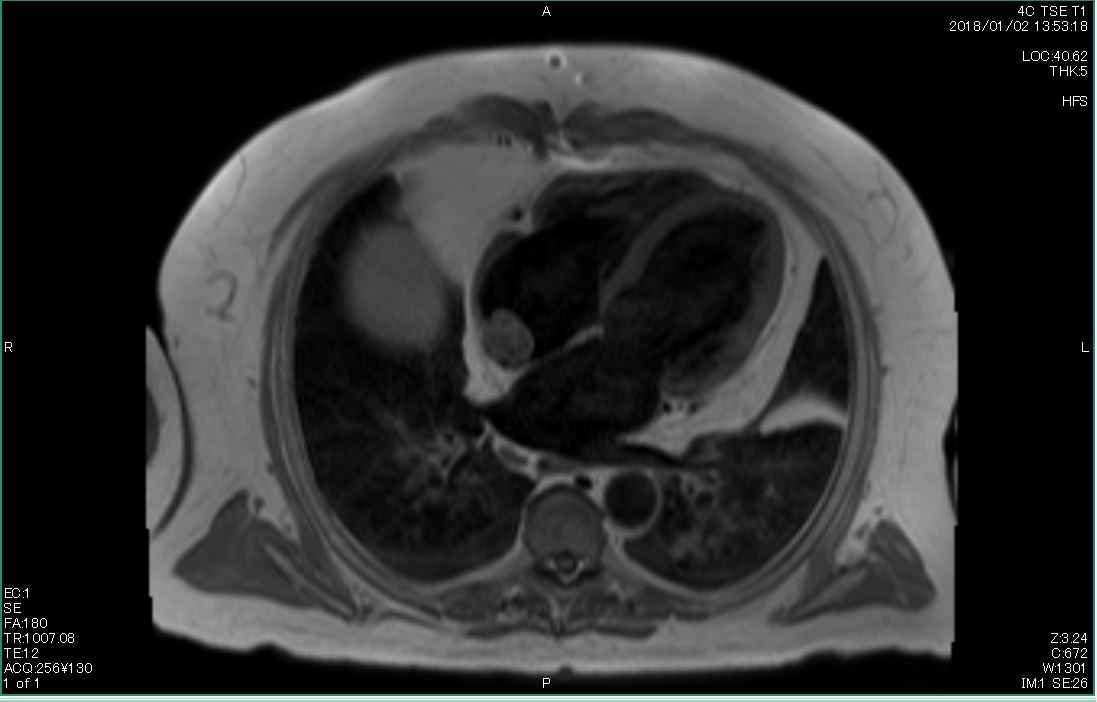

Cardiac MRI was performed on January 3, 2018, which revealed a large 2.5 × 2.9-cm lobular, fairly sessile mass in the right atrium. Without evidence of tissue destruction to suggest a malignant process, the lesion was suggestive of either myxoma or hematoma due to marked contrast uptake (which is seen less often with myxomas) (Figure 1).

Figures 1A-G. Cardiac MRI findings of a large, lobular, fairly sessile mass in the right atrium, measuring 2.5 x 2.9 cm, suggestive of either myxoma or hemangioma.